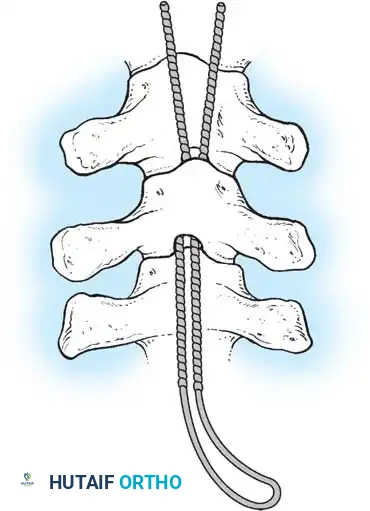

The Moe Technique (Thoracic Spine)

The Moe technique is a highly effective method for achieving intra-articular arthrodesis in the coronally oriented thoracic facet joints.

Fig. 38-26: The Moe technique of thoracic facet fusion, demonstrating the creation of hinged bone flaps.

- Expose the spine fully to the tips of the transverse processes.

- Using a sharp osteotome or Cobb gouge, begin a cut over the cephalad articular process at the base of the lamina.

- Carry this cut along the transverse process almost to its tip. Bend this cortical fragment laterally so it lies between the transverse processes, ideally leaving it hinged on its lateral periosteal attachment to preserve local vascularity.

- Thoroughly denude all articular cartilage from the superior articular process using a sharp curet.

- Make a secondary cut in the superior articular facet, working medially to laterally, producing another hinged fragment.

- Pack the resulting intra-articular defect tightly with cancellous bone graft.